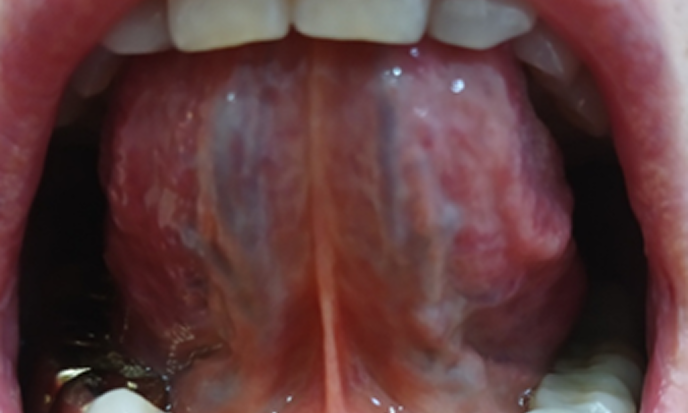

금진옥액사혈요법은

혀 밑에서 어혈을 빼내는 사혈 치료법으로 우리 몸의 혈액순환 장애 원인이 되는 어혈을 약물이나 수술 없이 몸 밖으로 배출하는 한의학적 치료법입니다.

금진옥액 혈에서 어혈을 적극적으로 제거하여 심혈관계 혈액순환 장애로 인한 각종 질병에 효과를 주며 특히 비만 체질이나 고혈압 환자의 심장 압박을 완화하는 데 보다 효과적입니다.

시선한의원에서는 금진옥액사혈요법과 함께 청혈해독 발효한약 복용, 경추기능활성 추나요법, 줄기세포활성 약침요법 등을 병행하여 심장과 두뇌의 혈액순환 개선뿐만 아니라 전신 말초 혈액순환 개선에도 우수한 효과를 보이고 있습니다.

금진옥액 사혈요법은 혈액순환의 장애 원인이 되는 어혈을 금진옥액이라는 혀 밑의 특수혈맥을 침도 침으로 자극하여

적극적으로 몸 밖으로 뽑아내는 사혈요법으로 혓바닥 아래의 금진옥액이라는 혈점의 울혈 부위를 절개하여

심혈관과 뇌혈관 내에서 원활하게 순환되지 않는 어혈들을 몸 밖으로 강력하게 뽑아냄으로써

평소 어혈로 인한 순환장애로 압박받는 심혈관과 뇌혈관의 혈액순환을 원활하게 하는 치료법으로,